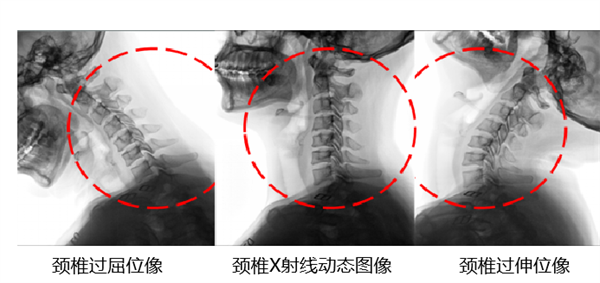

除了肺功能成像技术,部分厂家还基于动态DR开发除了骨科功能成像,通过分析骨骼关节的运动轨迹分析骨骼运动功能。例如颈椎的运动功能成像,可以通过AI图像处理算法提取患者动态椎体,对于椎体运动进行量化分析,通过标注每个椎体的运动,描述出每个颈椎的运动轨迹,通过运动轨迹的分析,可以为像滑溜(椎体错位)等颈椎疾病提供新的评估方式。这项技术有望在运动功能成像上为医生提供能好的辅助。